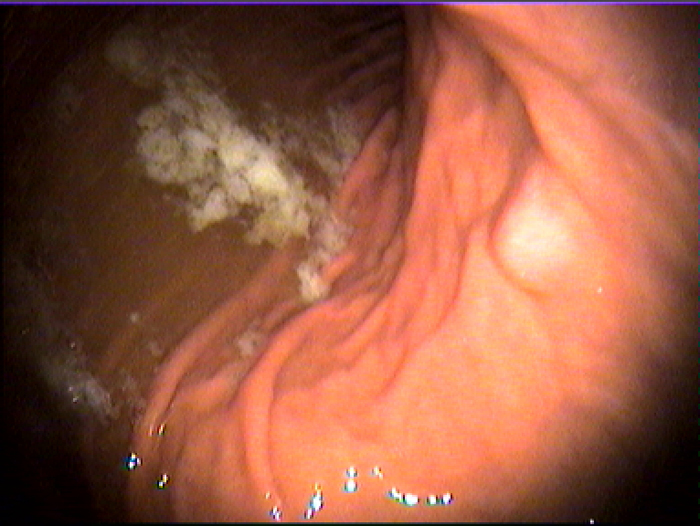

2、幽门螺杆菌感染:幽门螺杆菌感染引起慢性胃炎的证据如下:绝大多数慢性活动性胃炎患者胃粘膜可检出幽门螺杆菌,幽门螺杆菌在胃内分布与胃内炎症分布一致。